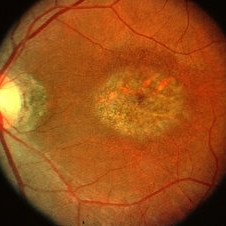

Late Stage Stargardt's Disease

Late Stage Stargardt's Disease

Mar 13 2013 by Hamid Ahmadieh, MD

Color fundus photograph of the right eye of a 46-year-old man with decreased VA due to advanced Stargardt's disease.

Photographer: Nayereh Hadipoor, Negah Eye Center, Tehran

Imaging device: Heidelberg Spectralis

Condition/keywords: Stargardt disease